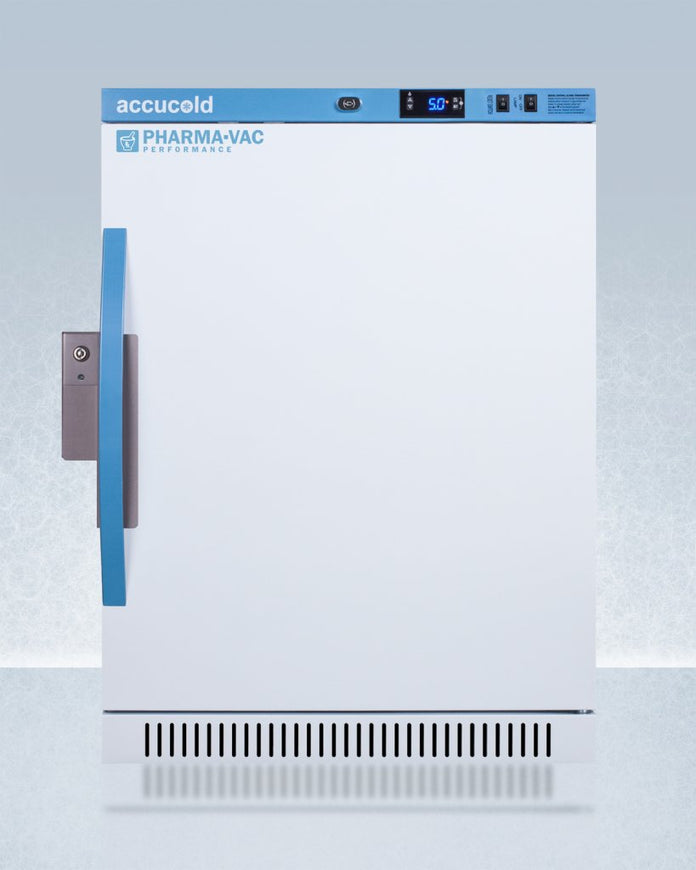

Accucold - ARS6PV-CRT - 6 Cu. Ft. ADA Height Upright Controlled Room Temperature Cabinet

Accucold's Performance Series Controlled Room Temperature Cabinets offer purpose-built storage solutions for medication requiring a stable room temperature environment.

The ARS6PV-CRT is a 6 cu.ft. upright unit pre-set to 72ºF, with an adjustable range from 68º to 77ºF. It is sized at 32.5 inches high for use in most ADA compliant applications. The microprocessor temperature controller is externally located to minimize door openings, helping to protect stored contents from ambient temperature. The buffered temperature probe is encased in a glycol-filled bottle to better simulate temperature of the stored product, with an additional sensor that reads air temperature to ensure superior temperature control. The current and min/max temperature display is viewable in Celsius or Fahrenheit to the nearest tenth of a degree. The audible and visual temperature alarm sounds if the unit's interior goes out of range. Additional alarms include a power failure alert, door open alarm, and sensor failure alarm. This unit is equipped with remote alarm contacts in the rear and a 1/2" probe port on the right side to accept additional monitoring devices. A hospital grade cord with 'green dot' plug is also included for added safety in high traffic areas.

The ARS6PV-CRT comes in a white cabinet finish with a blue accented control panel. The factory-installed antimicrobial handle is powder-coated with naturally occurring silver ions, which help to reduce the spread of germs, allowing for a safer, cleaner user experience. The user-reversible door ships with a right hand swing and self-closing function (note: self-closing is disabled once reversed to LHD). This model includes a factory-installed lock and ships with two keys for staff use. Powerful magnetic gaskets ensure a positive seal.